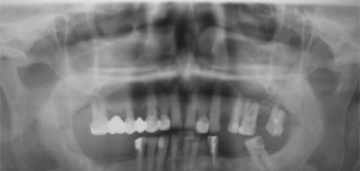

Рис.2. Ортопантомограмма пациента через два года после операции.

Через два года (рис.2, 4) после операции больной жалоб не предъявлял. Внешне асимметрии лица не наблюдалось. На ортопантомограмме наблюдалось восстановление костной ткани в области дефекта, хотя в центральных отделах дефекта плотность новообразованной кости уступала материнской.